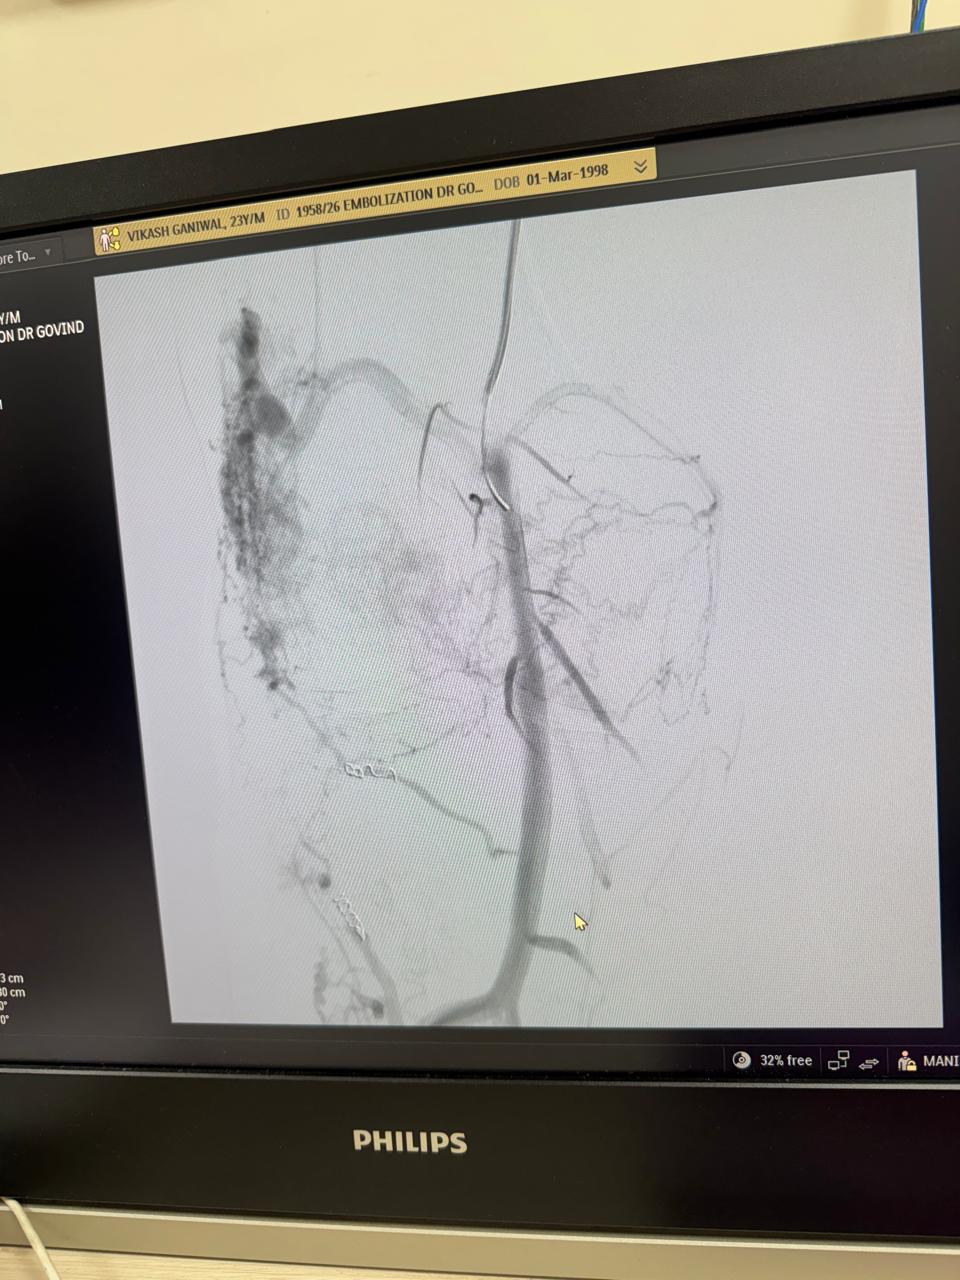

Vascular embolization of arteriovenous malformation